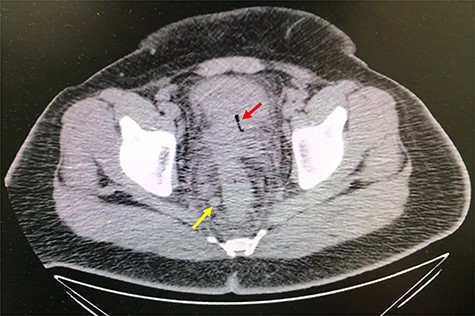

A 32-year-old man with no past medical or surgical history presented to the emergency department (ED) in April 2018, distressed and complaining of worsening pneumaturia for the past 3 days. The patient reported a 2-week history of polyuria, dysuria, suprapubic pain, tenesmus and inability to control his sphincters, prior to the ED-onset presentation. Further history revealed a 50-pound involuntary weight loss in a 5-month period, with partially treated urinary tract infections without resolution. He denied toxic habits, high-risk sexual behavior nor family history for colorectal cancer or inflammatory bowel disease. Based on the symptoms described, the rare triad of Gouverneur’s syndrome related to the EVF was considered. Physical evaluation revealed no palpable anorectal masses, adequate rectal tone and no visible gross blood. Urine analysis showed pyuria, hematuria, proteinuria with urine culture positive for Escherichia coli. Abdominopelvic computed tomography (CT) scan showed circumferential wall thickening of the rectum with surrounding fat stranding and numerous prominent pelvic lymph nodes (Fig. 1). Additionally, the scan showed pericolonic gas and fluid collection with a fistulous tract adjacent to the proximal rectum and the bladder (Fig. 2). In Figure 3, two hepatic hypodense lesions located in the right lobe of the liver were identified suggestive of metastasis. During colonoscopy, at approximately 20 cm from the anal verge a large, firm, irregular, friable, concentric mass was identified obstructing 95% of the lumen (Fig. 4). During surgery, the mass was not amenable for resection, due to its low pelvic location and size; a loop colostomy was performed for decompression, with liver tru-cut needle biopsy. Intraoperative cystoscopy was unsuccessful in placement of ureteral stents due to tumor invasion to the bladder.

Axial abdomen and pelvis CT scan showing enlarged lymph nodes (yellow arrow) and fat standing around rectum (red arrow).